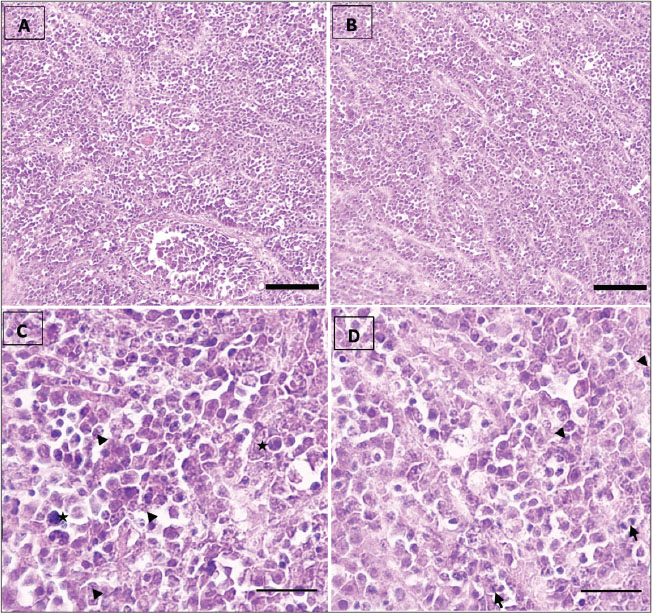

Fig. 1. Marked scrotal asymmetry in an adult stallion, characterized by a pronounced enlargement of the right testicle (A). Post-castration gross examination shows multiple lobulated masses of variable size and beige to dark beige color occupying most of the right testicular parenchyma (B) (asterisks), with whitish fibrous areas visible at the center of the section (white arrows). A well-demarcated hemorrhagic lesion is observed cranially to the left testis at the level of the epididymal head (C) (arrowhead), consistent with a localized hematoma, with an adjacent nodular lesion (asterisk). Anesthesia and surgical procedureThe stallion was premedicated with acepromazine (Calmivet®, Vetoquinol; 0.02 mg/kg body weight, IV). After approximately 20 minutes, sedation was induced using xylazine (Rompun®, Bayer; 0.8 mg/kg body weight, IV). General anesthesia was induced with ketamine hydrochloride (Ketamine®; 2.2 mg/kg body weight, IV) combined with diazepam (Diaphram®; 0.05mg/kg body weight, IV) and subsequently maintained with isoflurane (Aerrane®, Baxter) delivered via inhalation, as previously described by Muir et al. (2018). Preoperative analgesia was provided using flunixin meglumine (Norbrook®, Norbrook Laboratories; 1.1 mg/kg body weight, IV). Prophylactic antibiotic therapy consisted of benzylpenicillin sodium (Norbrook®, Norbrook Laboratories; 22.000 IU/kg body weight, IM). Castration was performed using a standard inguinal approach under routine aseptic conditions as previously described by Sedrish and Leonard (2001). The spermatic cord and cremaster muscle were isolated by blunt dissection, the testis was exteriorized, and the ligament of the tail of the epididymis was transected. An emasculator was applied to the spermatic cord for approximately 5 minutes prior to transection, followed by placement of a security ligature. The surgical site was closed routinely in two layers. Histopathological examinationRepresentative tissue samples from the testicular masses were fixed in 10% neutral buffered formalin for 48 hours to 5 days. Tissue specimens were processed routinely by dehydration through a graded series of ethanol solutions (70%–100%), cleared, and embedded in paraffin. Paraffin-embedded tissues were sectioned at a thickness of 3–5 µm, deparaffinized, and stained with hematoxylin and eosin (H&E) according to standard histological techniques as described by Bancroft and Gamble (2008). Histological sections were examined using a light microscope to evaluate the morphological characteristics of the testicular tissue and associated lesions. Post-castration examinationPost-castration examination of the right testis showed multiple firm, lobulated masses of varying sizes, occupying approximately the caudal two-thirds of the parenchyma (Fig. 1B). The combined diameter of the masses was approximately 14 cm. The remaining parenchyma contained scattered pale, irregular areas interspersed with zones that appeared relatively preserved (Fig. 1B). On the left side, a small, well-circumscribed 3-cm nodule was found above the left testis, along with a localized hematoma at the epididymal head. The cut surface of the neoplastic tissue was beige to dark beige in color and firm in texture, while the hemorrhagic area appeared dark red-brown, with partly clotted blood and mild compression of the adjacent parenchyma (Fig. 1C). These observations confirmed bilateral involvement, with lobulated neoplastic tissue in the right testis and a peri-epididymal nodule with focal hemorrhage on the left (Fig. 1B and C). Histopathological findingsExamination of the testicular parenchyma revealed a neoplastic proliferation with a diffuse architecture and trabecular architecture (Fig. 2A, B). The neoplastic cells exhibited enlarged, anisokaryotic, hyperchromatic, and nucleolated nuclei, with clear cytoplasm (Fig. 2C, asterisk). The stroma contained fibrous septa, infiltrated by lymphocytes occasionally forming lymphoid aggregates (Fig. 2B, white arrow). No vascular emboli were observed, and the epididymis, tunica albuginea, rete testis, and spermatic cord were free of neoplastic invasion. These morphological features were consistent with a seminoma.

Fig. 2. Histological sections of seminoma in the testis of an Arabian-Barbe stallion. A: Overview of seminoma showing the general lobular architecture of the tumor (H&E, ×10; bar=160 µm). B: Presence of fibrous trabeculae (white arrows) separating tumor lobules, illustrating the structural organization within the seminoma (H&E, ×10). C: Nuclear atypia within tumor cells, including karyorrhectic nuclei (arrowhead) and anisokaryosis (asterisk), indicating cellular pleomorphism and active tumor proliferation (H&E, ×40; bar=90 µm). D: Mitotic figure (black arrow) highlighting active cell division, a feature of tumor growth and malignancy (H&E, ×40; bar=90 µm). The nodular lesion was well-circumscribed and, on cut section, displayed a whitish, fasciculated appearance without evidence of gross necrosis. Histological evaluation of H&E-stained sections revealed a benign mesenchymal neoplasm composed of interlacing fascicles of spindle-shaped cells. The neoplastic cells exhibited elongated, uniform nuclei with finely dispersed chromatin and moderately eosinophilic cytoplasm, consistent with smooth muscle differentiation (Fig. 3C, D). The fascicular architecture was prominent, and the tumor stroma contained scattered thick-walled blood vessels. Mitotic activity was low, with two to three mitotic figures per ten high-power fields. No areas of tumor necrosis, cellular atypia, or other features suggestive of malignancy were observed, supporting the diagnosis of leiomyoma.